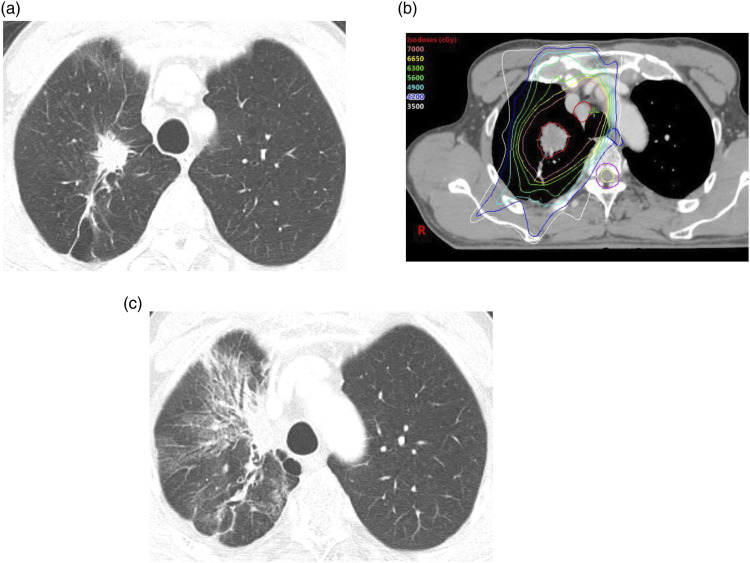

Materials and methods: We reviewed data from 240 NSCLC patients who underwent RT between 2014 and 2022. CT findings of RP were evaluated for parenchymal abnormalities and distribution, which were then classified into three patterns: localized pneumonia (LP), cryptogenic organizing pneumonia (COP), and acute interstitial pneumonia (AIP). Clinical outcomes of RP were evaluated based on Common Terminology Criteria for Adverse Events (CTCAE) grade.

Results: Of the 153 patients, 135 developed RP. The most common pattern was LP (n = 78), followed by COP (n = 30) and AIP (n = 25). Among the three CT patterns, CTCAE grade and days between the start of RT and the onset of RP (RT-RP days) were statistically significantly different (p < 0.05). The patients with AIP patterns exhibited higher CTCAE grade, and fewer RT-RP days compared to those with non-AIP patterns (p < 0.05). In these patients, lung-to-lung metastasis and underlying interstitial lung abnormality were observed more frequently (p < 0.05). Underlying pulmonary fibrosis, the AIP pattern, and higher CT extent scores were more frequently observed in higher CTCAE grade group (p < 0.001). In multiple regression analysis, age, bilateral distribution, RT-RP days, and CT extent score ≥3 were independent predicting factors for higher CTCAE grade.

Conclusions: RP in NSCLC patients can be classified into LP, COP, and AIP patterns and they exhibit different severities in clinical outcomes.